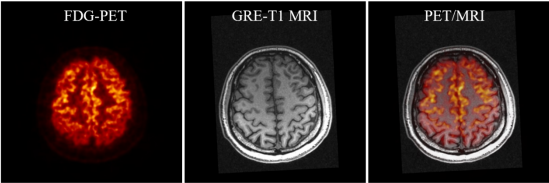

SIAT bPET和聯(lián)影uMR790 3T磁共振成像系統(tǒng)上同時(shí)獲得的人腦PET/MRI圖像

據(jù)了解,PET和MRI都是腦科學(xué)研究和腦疾病診斷的重要工具,PET的高靈敏度、高定量精度功能代謝成像和MRI的高空間分辨率、高軟組織對(duì)比度解剖結(jié)構(gòu)成像高度互補(bǔ),PET和MRI還可以相互輔助,進(jìn)一步提升各自的腦神經(jīng)成像能力。

PET分子成像通過測(cè)量大腦的血流、葡萄糖和氧的代謝、蛋白質(zhì)的生成、藥物的分布和神經(jīng)遞質(zhì)的動(dòng)力學(xué)等,探索不同腦區(qū)的功能,確定病變腦區(qū)的功能演變,對(duì)于腦疾病干預(yù)治療策略和新藥物探索具有重要意義。